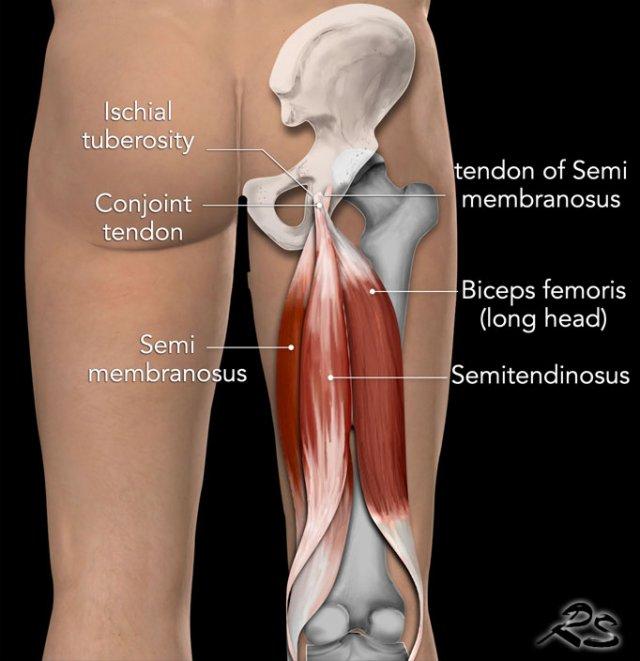

Giải phẫu

Cơ nhị đầu đùi

Cơ nhị đầu đùi có hai đầu.

Đầu dài xuất phát từ ụ ngồi, trong khi đầu ngắn xuất phát từ đường ráp (linea aspera) ở mặt sau xương đùi.

Gân chung của hai đầu có thể sờ thấy ở phía ngoài vùng khoeo và bám tận vào chỏm xương mác.

Cơ bán gân

Cơ bán gân là cơ có phần gân chiếm ưu thế, nằm ở phía trong so với cơ nhị đầu đùi và che phủ phần lớn cơ bán màng.

Cơ bán màng

Cơ bán màng có hình dẹt và rộng, nằm bên dưới cơ bán gân.

Hình ảnh giải phẫu được minh họa trên ảnh MRI mặt phẳng coronal.

Các cơ gân kheo bám tận vào vùng trên của ụ ngồi.

Trên hình ảnh nhìn từ phía sau, có thể thấy gân cơ bán màng bám vào phía ngoài trong khi thân cơ lại nằm ở phía trong.

Gân chung của cơ nhị đầu đùi và cơ bán gân bám vào diện trong (medial facet).